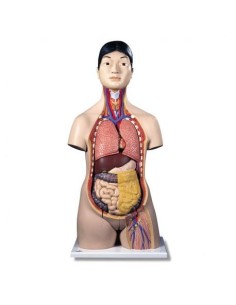

Scopri il Mondo dell’Anatomia con Modelli anatomici di Precisione

Modelli Anatomici Dettagliati per Ogni Necessità

Dal cranio in 22 parti con incastri magnetici ai modelli di colonna vertebrale, da quelli di articolazioni a quelli di cuore, ogni pezzo della nostra collezione è progettato per un’immersione totale nello studio dell’anatomia umana. I nostri modelli, realizzati tramite scansioni di ossa vere, garantiscono un’esperienza tattile autentica e una fedeltà di peso quasi identica agli originali.

Strumenti Didattici Innovativi per l’Educazione e la Pratica Medica

Essenziali per studenti e professionisti, i nostri modelli anatomici sono strumenti didattici che permettono di osservare le strutture anatomiche con precisione, eliminando la necessità di dissezioni o studi invasivi. Sono inoltre utili per spiegare ai pazienti le patologie, rendendo la comunicazione più efficace e risparmiando tempo prezioso.